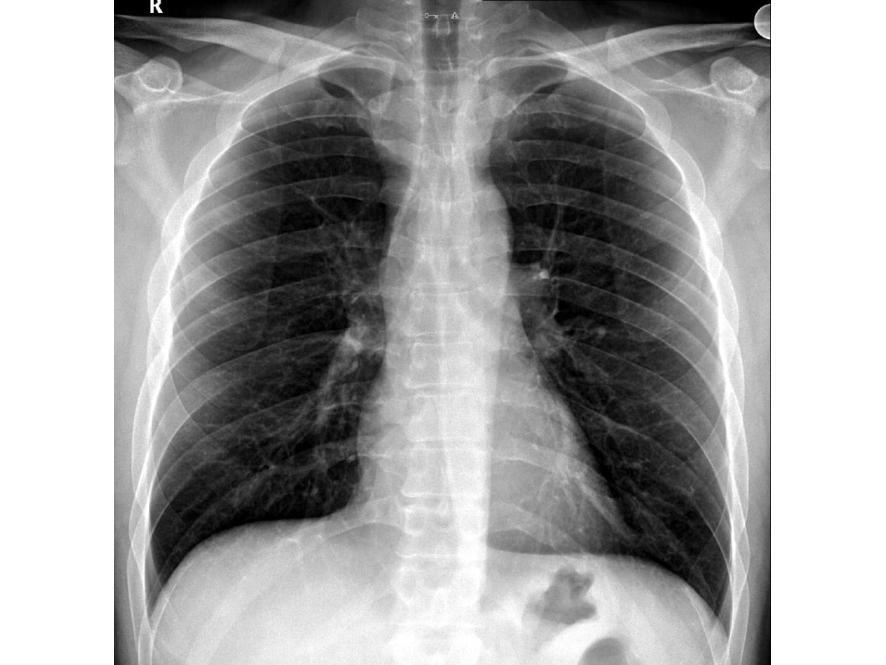

Torasik Outlet Sendromu Rontgen

Torasik Outlet Sendromu Rontgen - What is thoracic outlet syndrome?